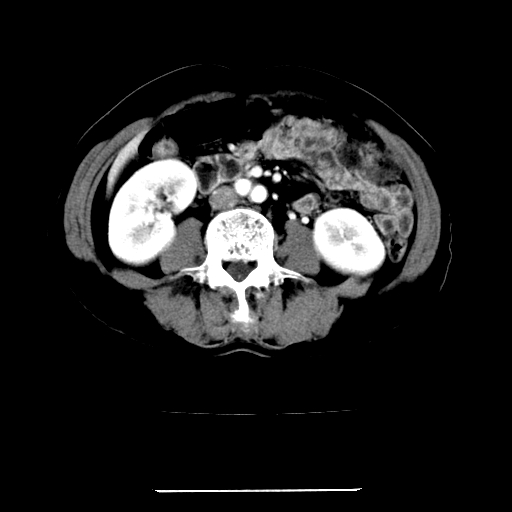

女,67岁,上腹部疼痛一周伴皮肤黄染,无发热。

左叶肝内胆管结石,并远端肝内胆管扩张。

考虑:肝内胆管结石继发肝内胆管扩张,右肾旋转不良。

肝内外胆管结石并肝内胆管扩张。

1、肝门高密度影下层面和胰头层面可见轻度胆管扩张,而静脉和延迟期均未见扫描完胰头,不能完全排除胰头占位。2、肝门部高密度影,考虑钙化或结石。

考虑肝门胆管癌伴门脉左支受侵包埋,建议mrcp进一步检查。